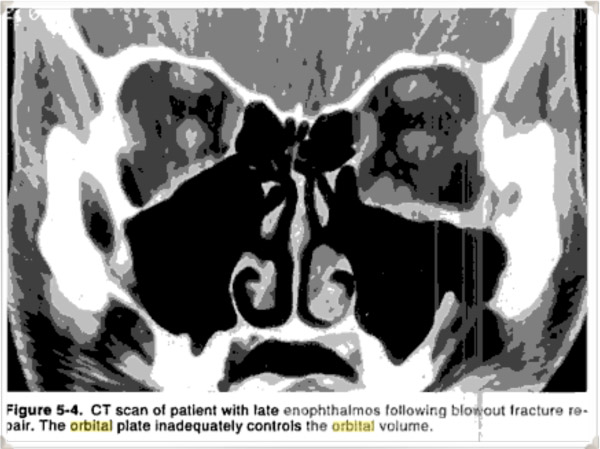

Surgery must restore the orbital volume and requires careful isolation of stable bone on all sides of the fracture and adequate fixation of appropriately sized alloplastic or autogenous implants. If inadequate stable bone is identified, the use of rigid fixation systems can provide the necessary stabilization to control the position of the implants. A common mistake is to fail to realize that the normal inferomedial orbit, rather than being concave away from the orbit is actually convex towards the orbit; this postequatorial convexity must be re-created to avoid expansion of the orbital volume. This problem is demonstrated by the CT scan and clinical outcome in a 21-year old patient referred with persistent enophthalmos following a blowout repair. […] The CT scan demonstrated that the orbital plate rested on the floor but failed to recreate the postequatorial convexity, so that the orbit had the shape of a box instead of a triangle. The orbit was expanded, resulting in postoperative enophthalmos.

And the relevant image that the textbook refers to:

- A common mistake is to fail to recreate the proper contour of the orbital floor. If it looks like a box instead of a triangle, it’s not right. And that’s what both my CT and MRI show from both surgeries.